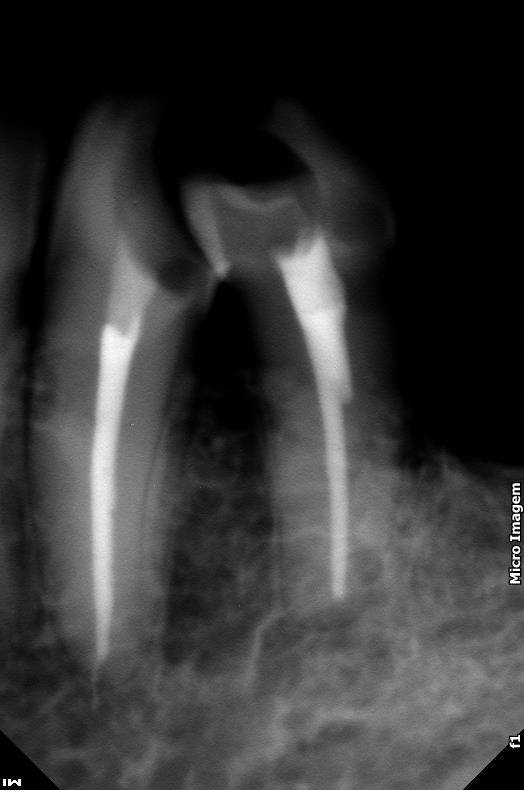

Nesse mesmo dia poderá ser realizado o procedimento de abertura coronária e acesso, tudo feito sob anestesia, realizando a limpeza do canal e medicação quando necessário

Preparação dos canais, limpeza e desinfecção, irrigação e obturação dos canais de maneira precisa, selando com material biológico biocompatível